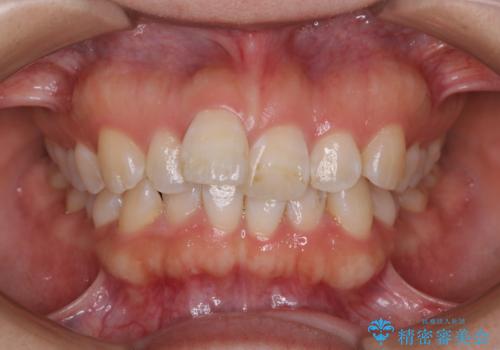

- 上顎の八重歯が気になるとのことで来院されました。

左側のかみ合わせは、歯1本分かみ合わせが前にずれていました。上顎左右の奥歯を2本抜歯しています。

下顎は、歯の側面を少し削ることで歯並びを整えました。

八重歯でがたつきは重度でしたが、きれいな歯並びにすることができました。

がたつきだけでなく、奥歯の噛み合わせのずれの調整もしっかり行いました。